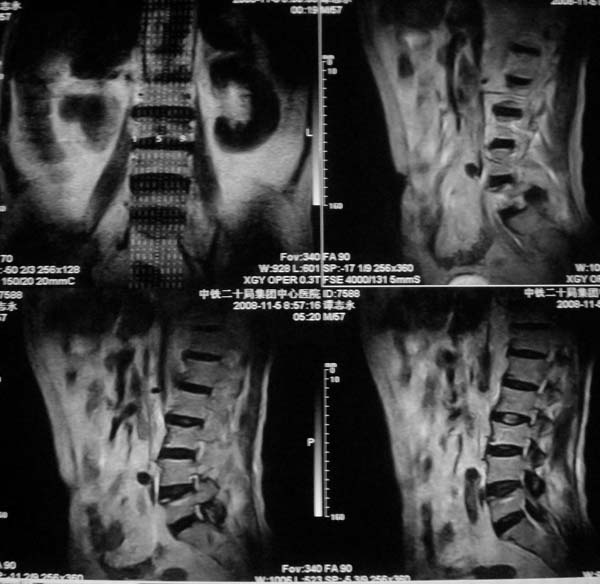

病史特点:

1.中年男性

2.腰疼,双下肢麻木1月。

3.ct 可右肾上腺占位,腰1椎体及附件可见骨质破坏及软组织肿块。

4.mri:腰1椎体及附件t1wi低信号,t2wi高信号。

考虑右侧肾上腺癌骨转移.或右肾上腺及骨均为转移瘤。